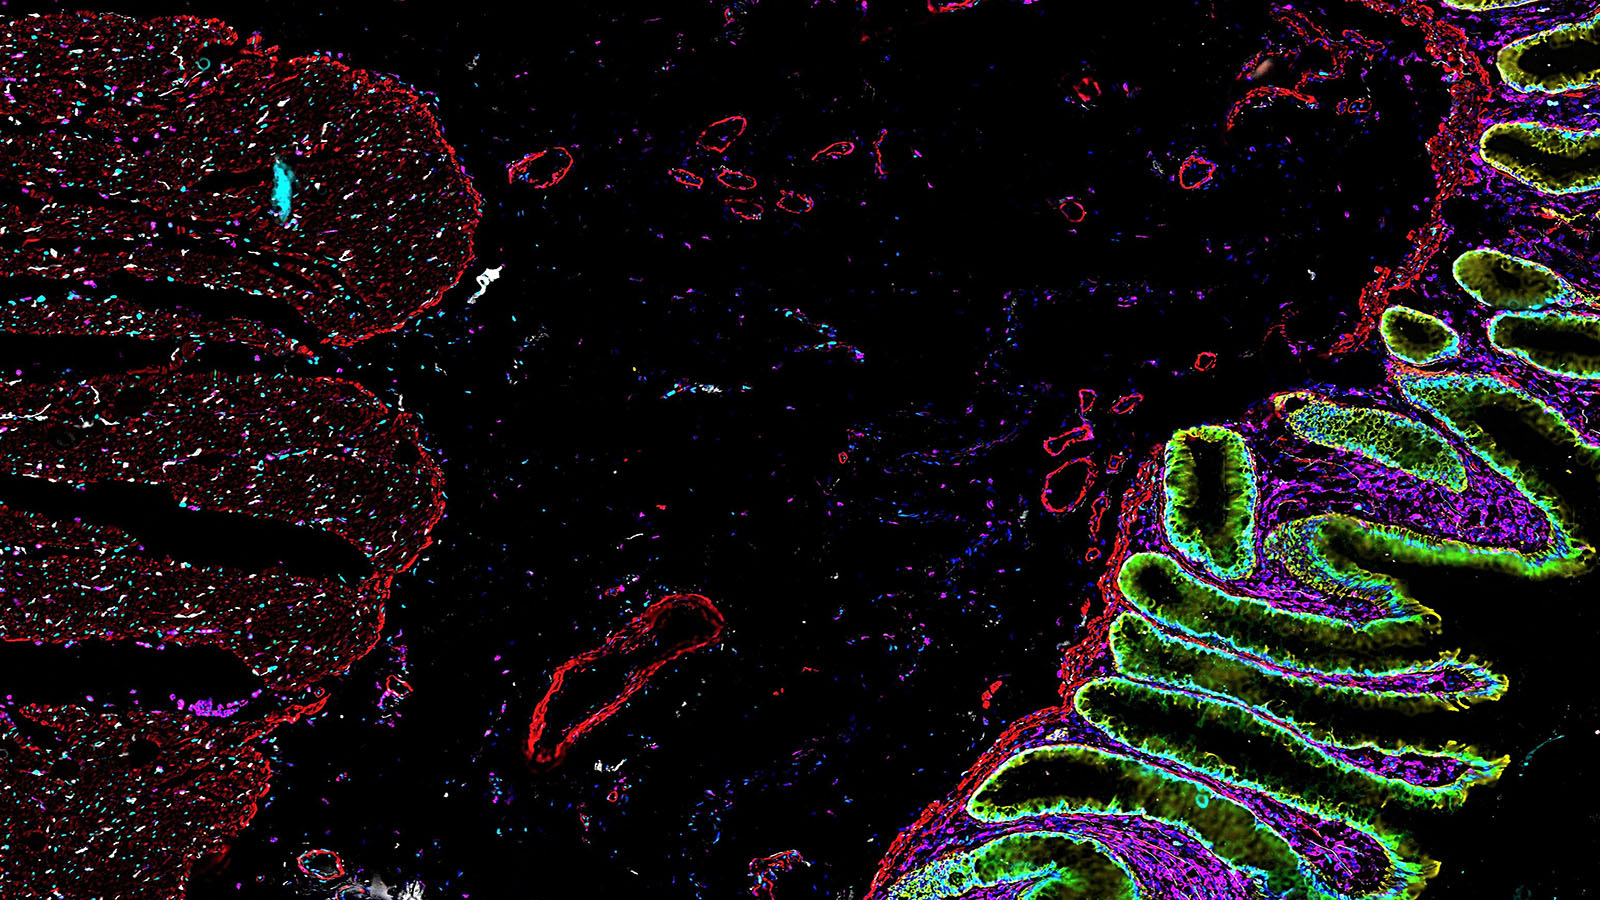

Human colon cells made by the researchers at Stanford University's Bendall lab that uses single-cell metabolic regulome profiling (scMEP).

CODEX of healthy colon, courtesy of John Hickey at Stanford

The lining of the uterus & fetal cells within & around maternal spiral arteries, courtesy of Dr. Michael Angelo at Stanford

7 proteins in a section of healthy human colon tissue, courtesy of Dr. John Hickey at Stanford